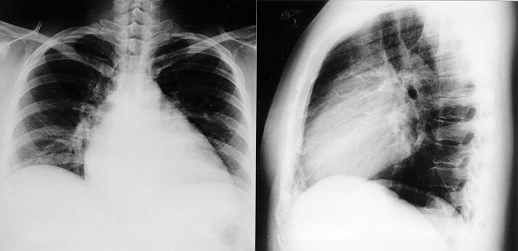

X光片